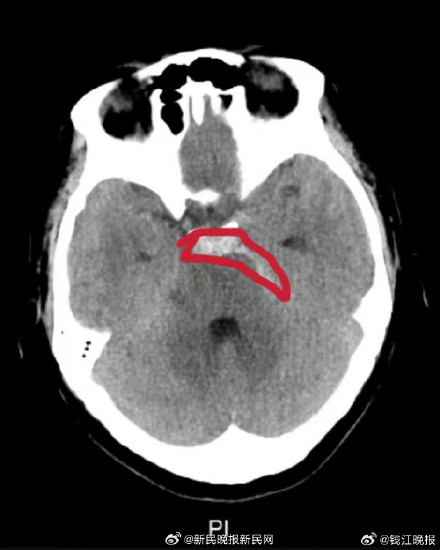

近日,董女士在辅导二年级女儿的作业时,又难免情绪上头。 她突然感觉头痛欲裂,还直犯恶心,在卫生间干呕了一阵之后,她起初以为是最近上班太累了,可休息了一晚情况仍未好转,熬了一阵子后,觉得情况不对的她之后就近来到杭州师范大学附属医院就诊,接诊的神经外科裘五四主任医师为她安排做了头部CT,结果显示:蛛血,建议复查。

拿着检查报告的董女士怎么也想不通,身体健康的自己,怎会脑出血? “幸好董女士的颅内出血量不算多,只需接受保守治疗,注意观察为主,无新发出血可出院。”裘五四主任医师反复强调,住院期间必须保持心情平和,切勿激动,注意休息。目前,董女士已顺利出院。 via潮新闻